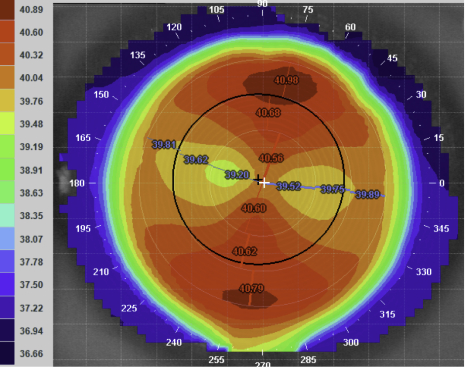

Refraction was R -2.00/-0.25 x 90 (6/5), L -1.25/-6.50 x 132 (6/20+). Corneal topography revealed an essentially normal pattern in the right eye and a steep central area with surprisingly regular astigmatism in the left eye. Keratoconus was confirmed with pachymetry showing relative thinning in the left eye: R 562µm, L 530µm. Slit-lamp examination revealed no corneal opacity in either eye.

Axial maps of the right and left eye showing the significant curvature difference between the two eyes.

Axial over-topography of the final front-surface toric lens, nicely showing the -1.25D of astigmatic correction incorporated sitting with axis of 85